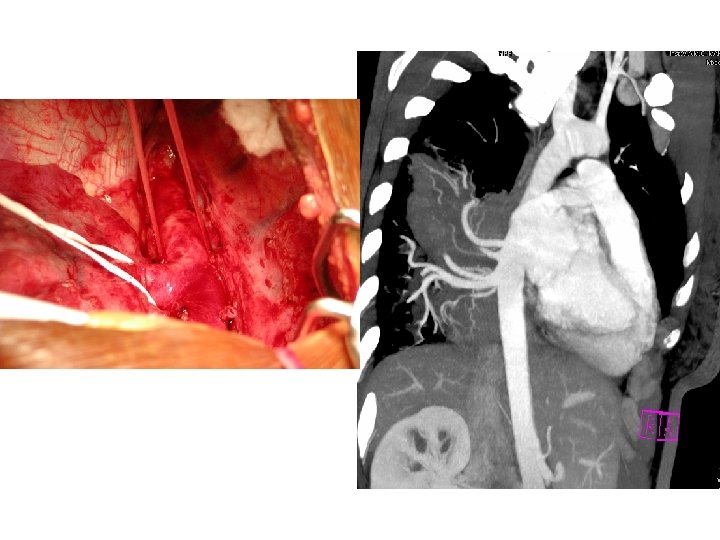

Surgical Report • Intralobar Pulmonary Sequestration, treated with right lower lobectomy • Two major arteries from the thoracic aorta • Large vein draining sequestered lobe

Intralobar Pulmonary Sequestration (ILS) Characteristics • More common type • May present at any age • Generally as recurrent infection • No sexual predominance • Almost exclusively affects lower lobe • Arterial supply: descending aorta • Venous drainage: pulmonary veins

Treatment of Pulmonary Sequestration Symptomatic Disease • Surgery: lobectomy or segmental resection • Arterial embolization